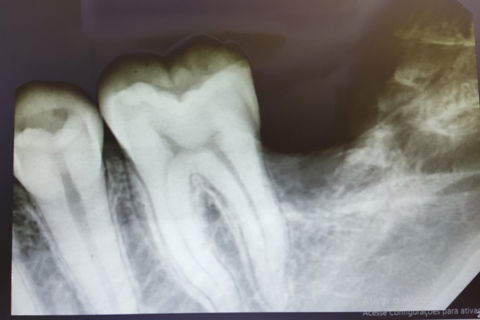

Região do 37/38

raio-x imediato pós exo 37/38